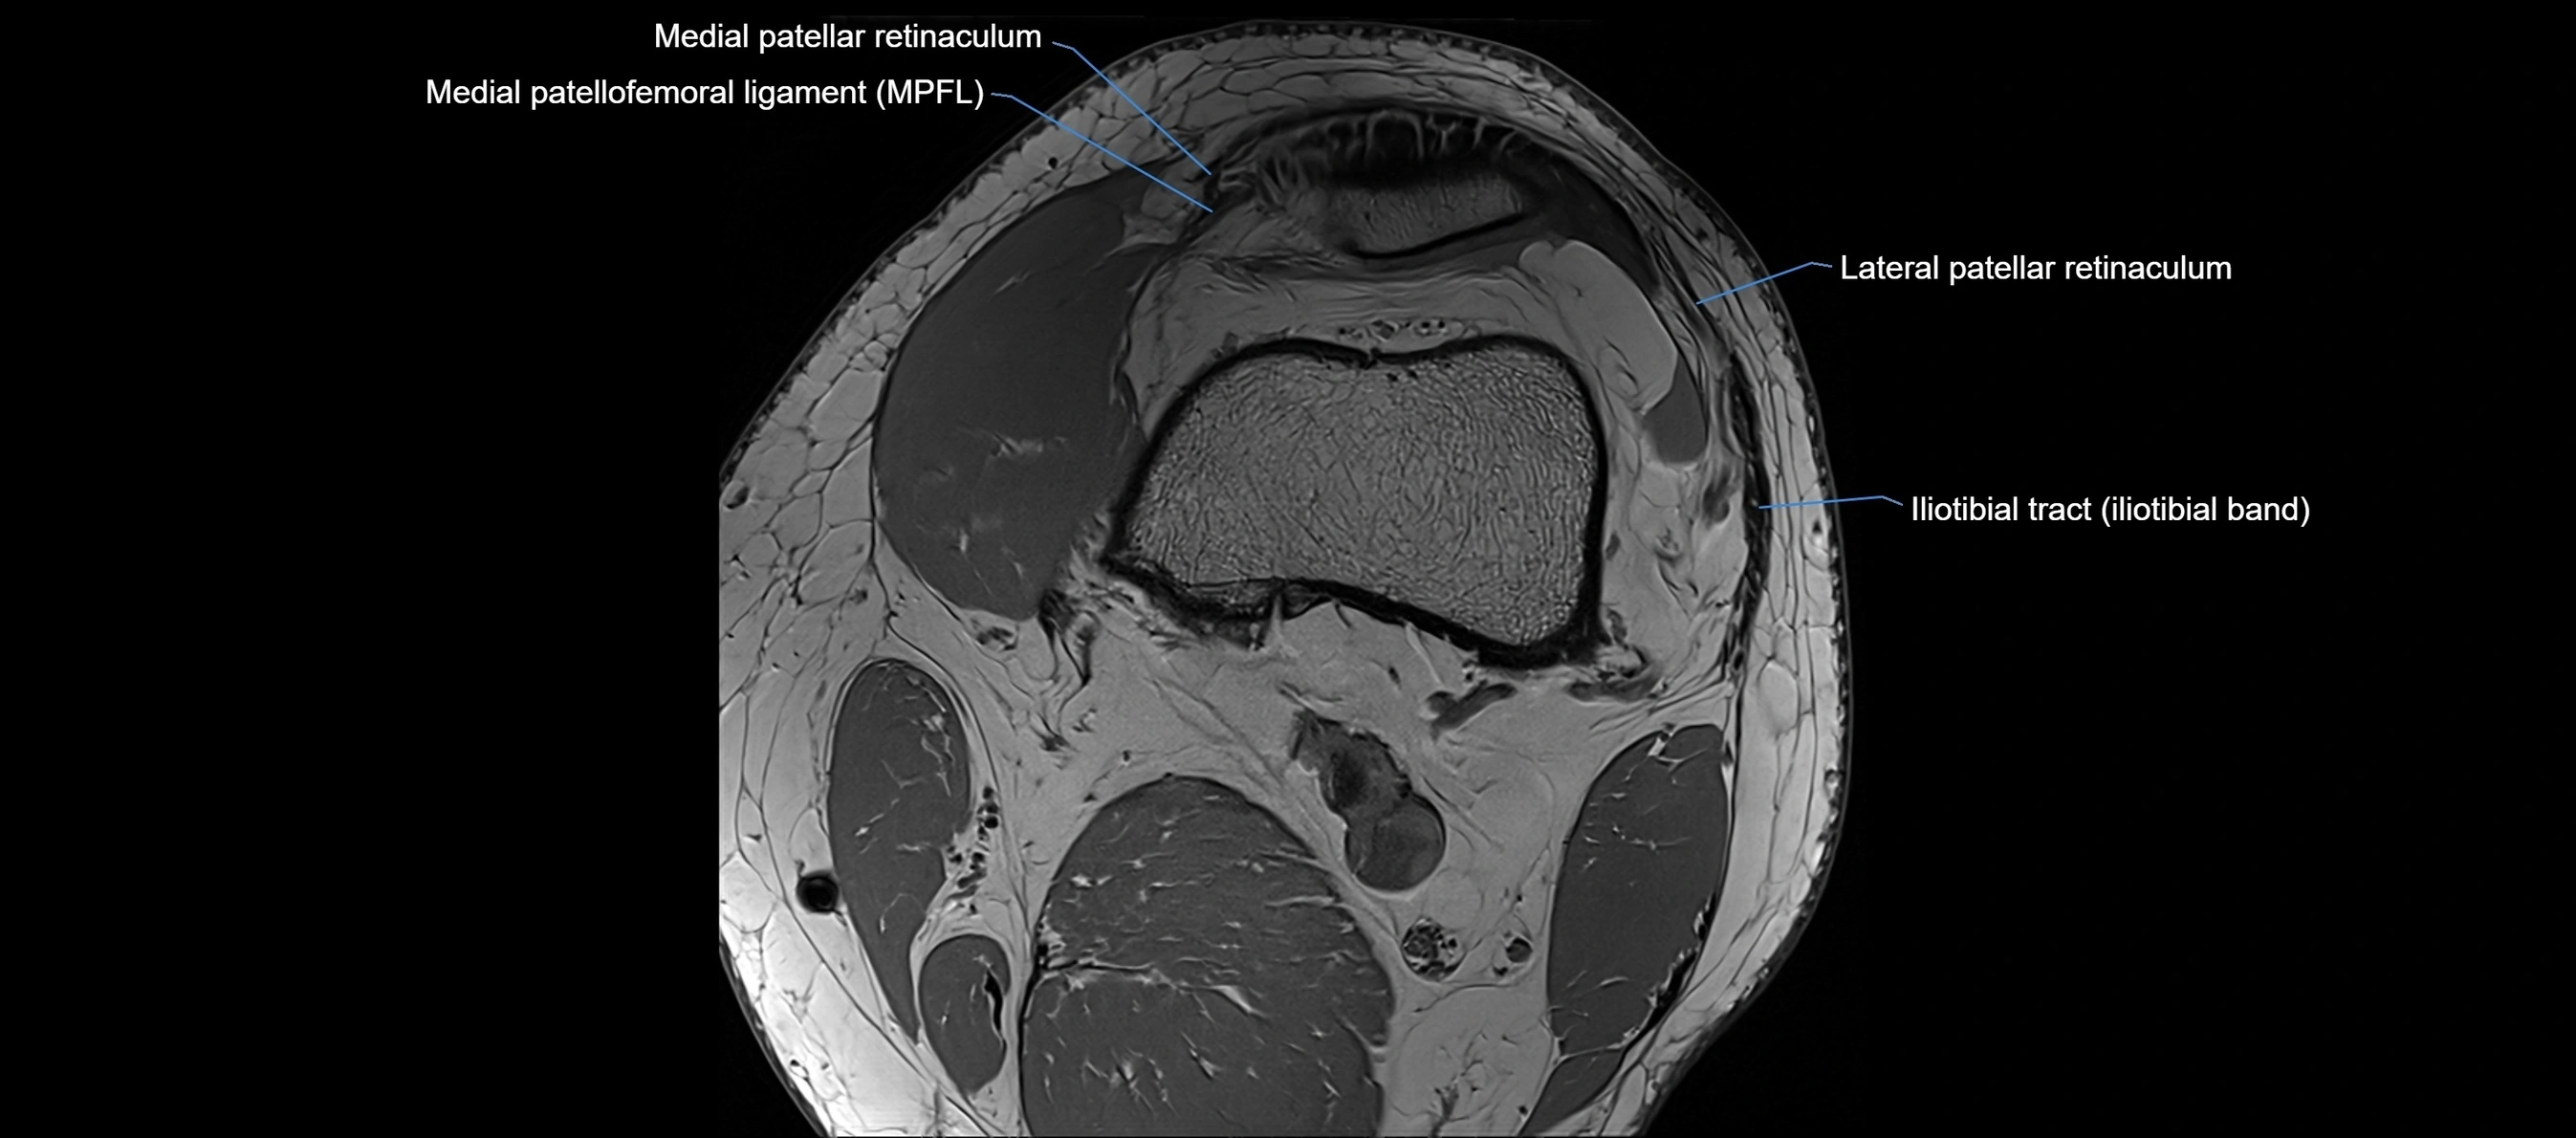

MRI images

image